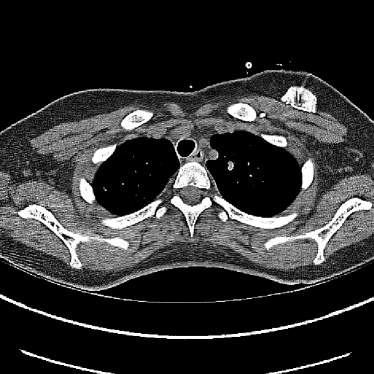

Figure 14: Qualitative clinical results from a thoracic CT staging dataset for a 12-year-old with osteosarcoma with pulmonary metastases. The clinical standard hybrid IR is shown on the left and JENG is on the right. (a) The clinical standard hybrid IR in lung window with a window center of -600 HU and a window width of 1500 HU. (b) JENG at a resolution comparable to the clinical standard, but with less noise and fewer artifacts. (c) The clinical standard hybrid IR in soft tissue window with a window center of 55 HU and a window width of 440 HU. A metastatic lung cancer nodule can be found in the left upper lobe. (d) JENG in soft tissue window at a comparable resolution, but with less noise and fewer artifacts. Note that JENG is not fully corrected for beam hardening artifacts.

V.B. Clinical Cases

None of the spatial resolution and artifact reduction advantages would hold unless JENG shows image quality improvement over the clinical standard method on patient datasets. To do so, we evaluated JENG on 5 thoracic and 3 abdominal CT scans and all scans used the same parameter settings as those for the ACR phantom scan, except that the tube current and the pitch is modulated individually for each patient. The exact experiment setup was discussed in Sec. IV.. For a fair image quality comparison, we matched the resolution of JENG and the clinical standard hybrid IR and studied their image noise and artifacts.